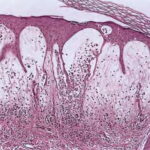

Atlas of skin histopathology

Bullosis diabeticorum = فقاعات مرافقة للداء السكري